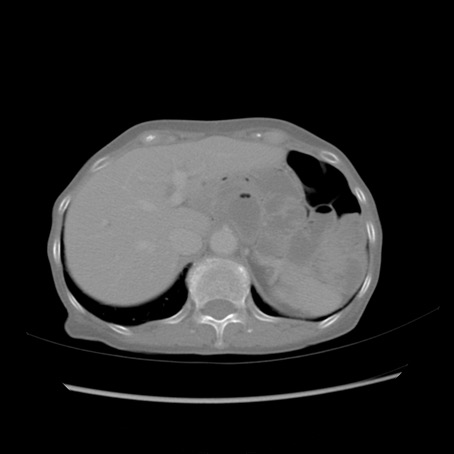

症例25(横断像)

【症例】80歳代女性

【主訴】胸のつかえ感

【現病歴】約9時間前に食後から胸のつかえた感じあり、嘔吐あり、来院。

【既往歴】胃癌(全摘)、胆摘、虫垂炎

【身体所見】心窩部に圧痛あり、反跳痛なし。

【データ】WBC 5700、CRP 0.05